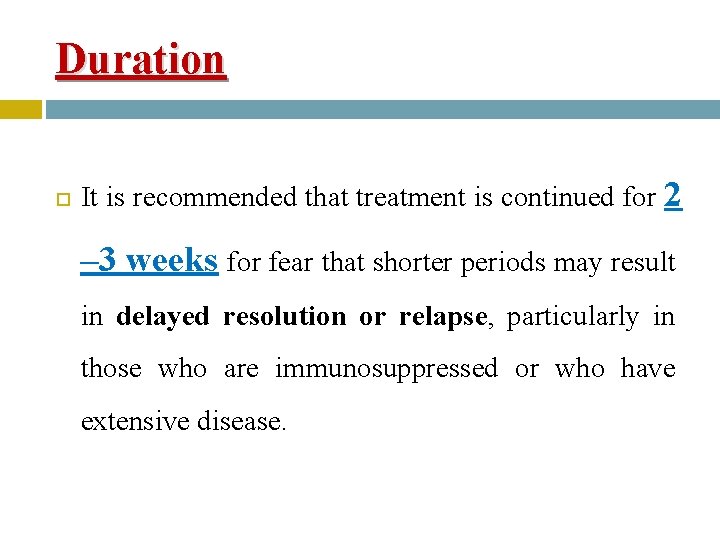

Duration It is recommended that treatment is continued for 2 – 3 weeks for fear that shorter periods may result in delayed resolution or relapse, particularly in those who are immunosuppressed or who have extensive disease.